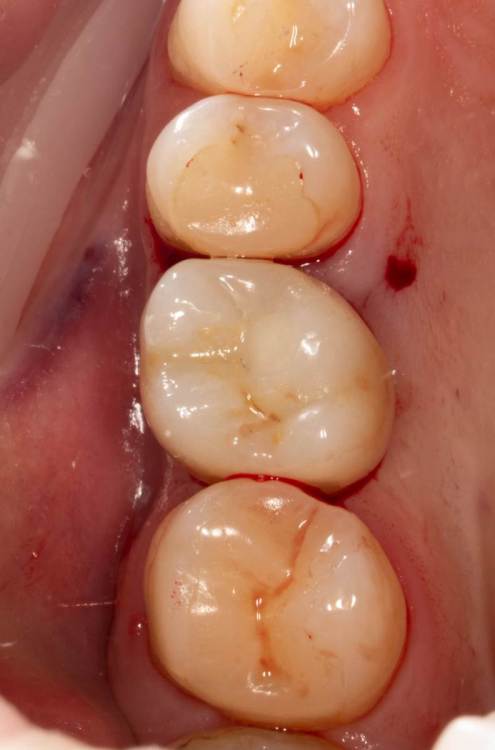

Женька Опубликовано 23 июля, 2022 Автор Поделиться Опубликовано 23 июля, 2022 (изменено) Кончилось вот так в общем. Сразу после фиксации. Коллеги, обойтись без разрезов на постоянных коронках можно только посредством временных? Изменено 23 июля, 2022 пользователем Женька 4 Ссылка на комментарий

Aquarius Опубликовано 23 июля, 2022 Поделиться Опубликовано 23 июля, 2022 (изменено) Ну это же шоколад для ортопеда. Дави не хочу. И шахту прилично заопачили. Респект. Она обычно колхозно светится Изменено 23 июля, 2022 пользователем Aquarius Ссылка на комментарий